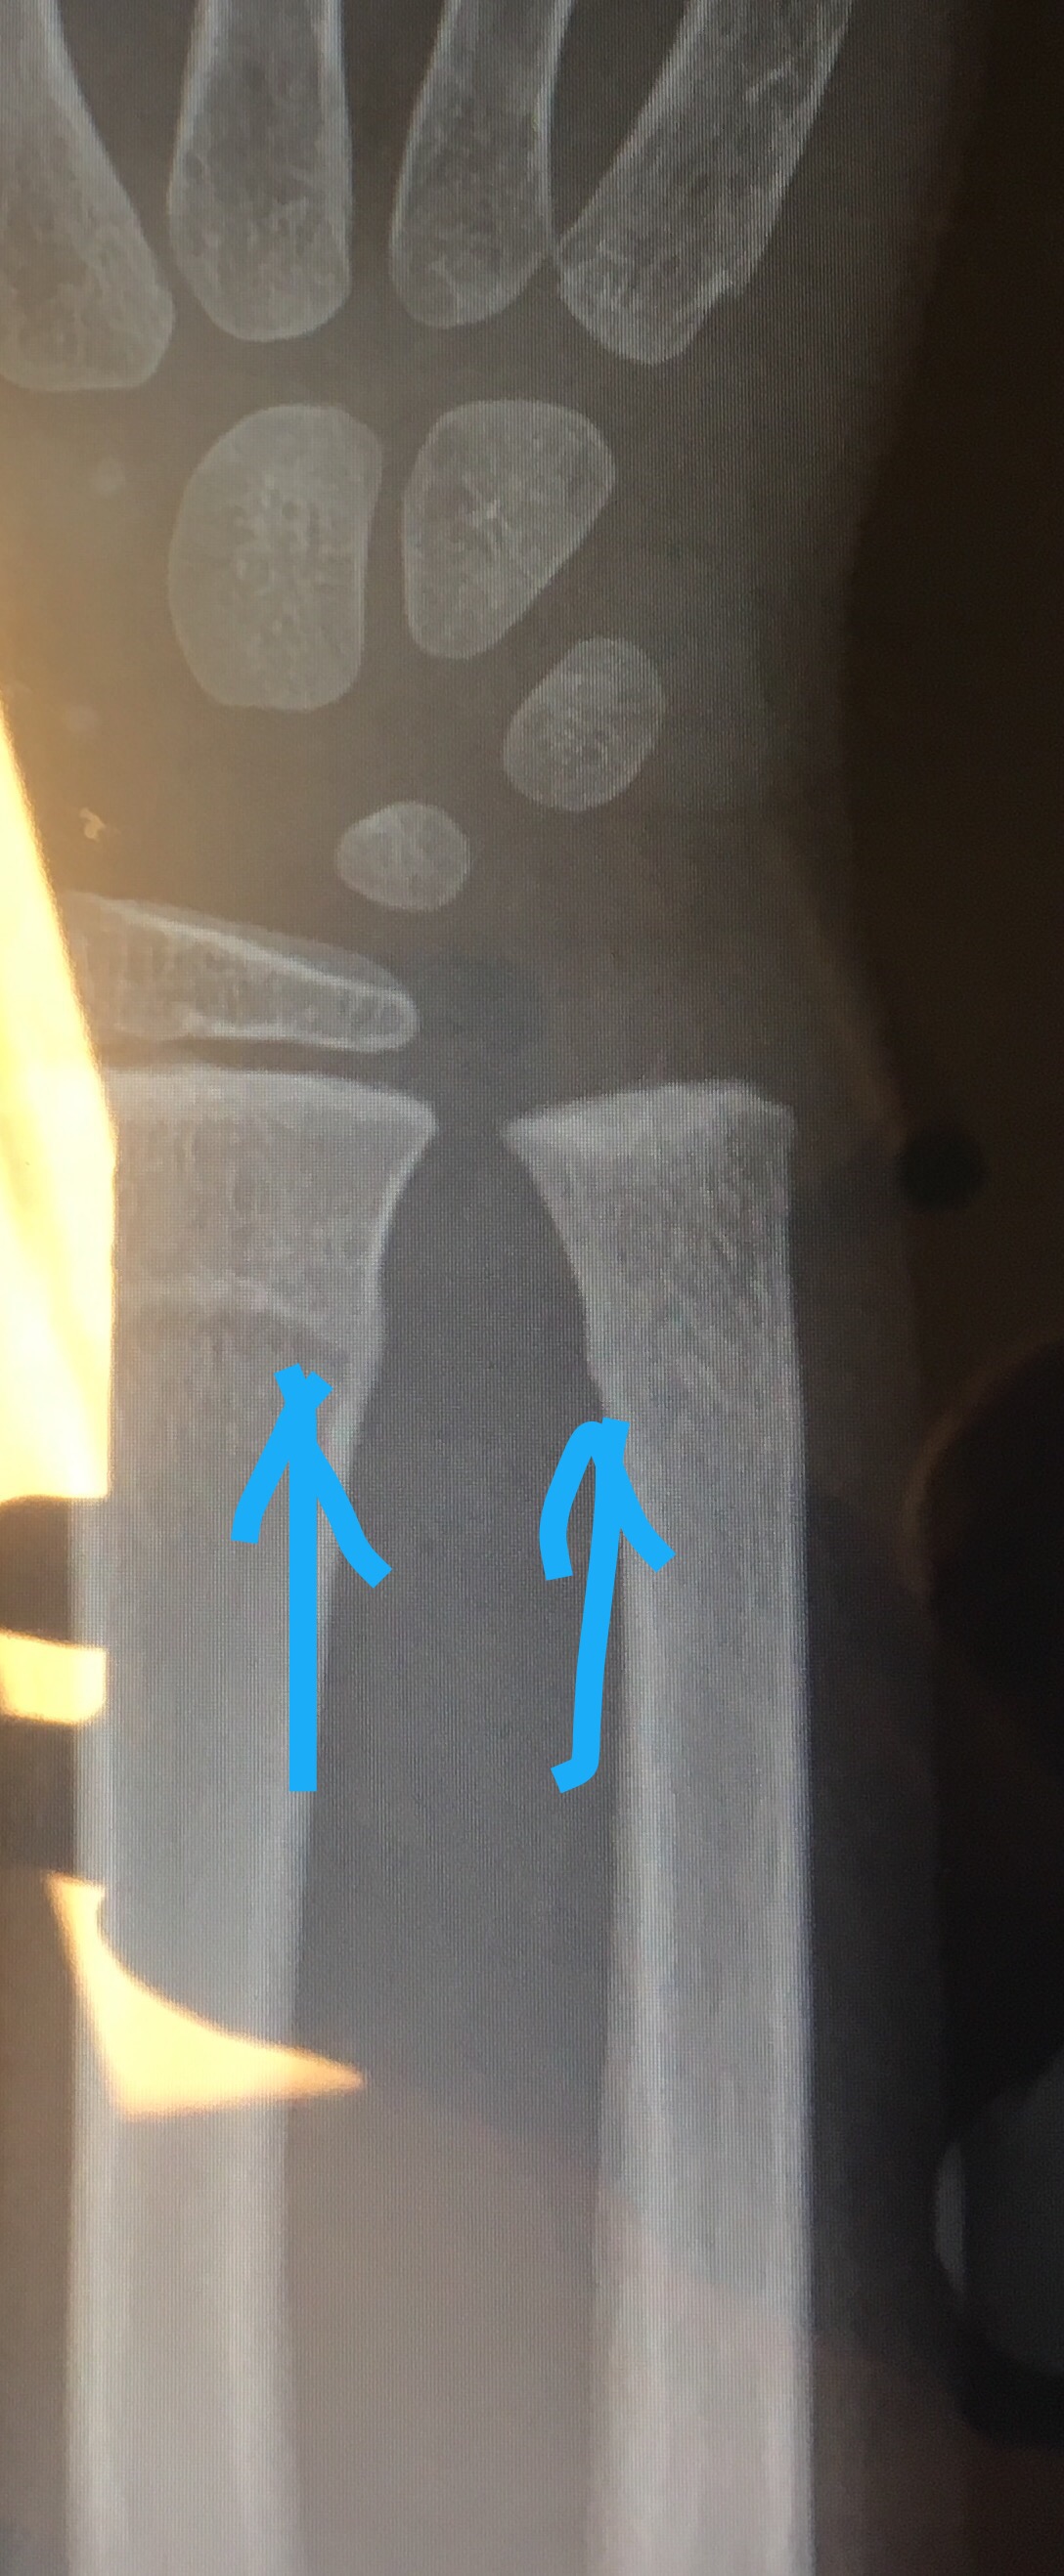

Poor little Oscar fell off his bed ladders and broke his right arm just over a year after he broke his left arm. Tough guy